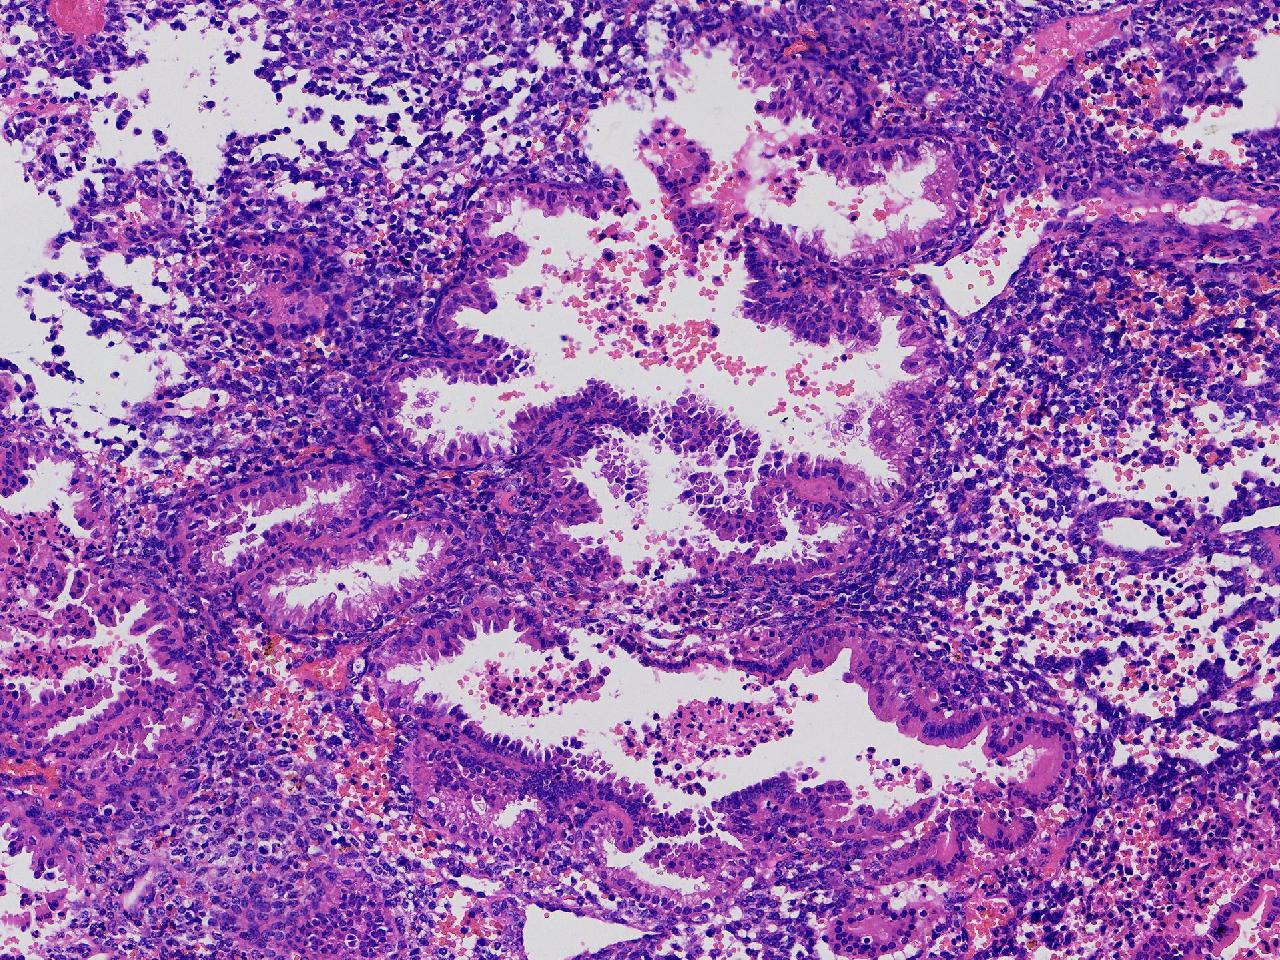

性别

女

年龄

45岁

临床诊断

阴道不规则出血20余天,

一般病史

彩超示:宫腔内见约41X11毫米的不均质回声区。宫腔镜示:宫腔形态正常,内膜粉红,不规则增厚。

标本名称

子宫内膜

大体所见

灰粉色不整形软组织多块,1.5X1X0.6厘米。

分泌反应子宫内膜,伴有出血。

晚泌期及月经早期改变,局部呈啫酸性乳头状化生改变。